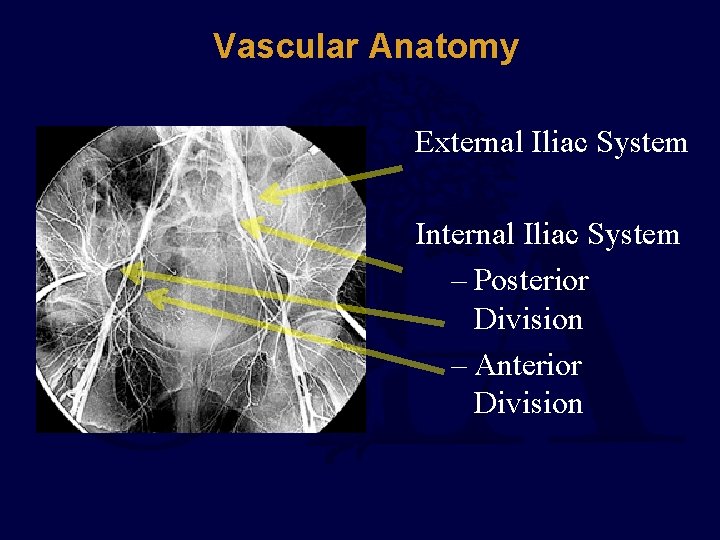

Vascular Anatomy External Iliac System Internal Iliac System – Posterior Division – Anterior Division